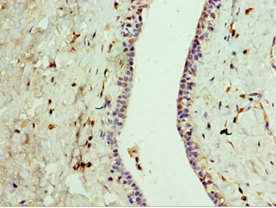

Immunohistochemistry of paraffin-embedded human breast cancer using CSB-PA818781DSR1HU at dilution of 1:100